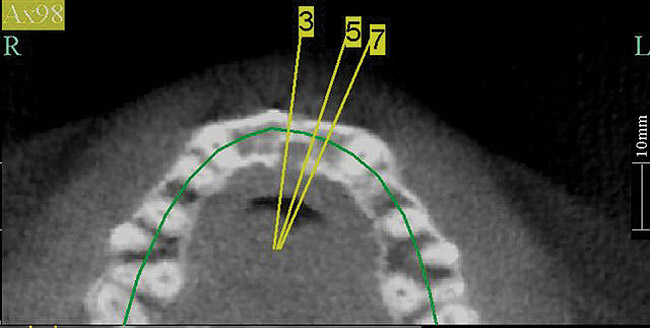

Figure 17   Volumetric characterization of the residual alveolar ridge using CBCT: Fig 17 The coronal section of the maxilla reveals the cortical structure of the alveolar ridge associated with the missing right central incisor at the mid-root level. The buccal plate is identifiable and is characterized by little resorption. Fig 18  The saggital section of the maxillary alveolar ridge is displayed in relationship to the planned contour of the eventual implant crown. Fig 19 Importing DICOM files into planning software permits evaluation of the implant, abutment, and crown relationships with existing bone. These images readily characterize both the possible 6-mm mesiodistal width and the possible displacement of the implant 3-mm apical and 2-mm palatal to the planned gingival zenith.

Figure 19    Volumetric characterization of the residual alveolar ridge using CBCT: Fig 17 The coronal section of the maxilla reveals the cortical structure of the alveolar ridge associated with the missing right central incisor at the mid-root level. The buccal plate is identifiable and is characterized by little resorption. Fig 18  The saggital section of the maxillary alveolar ridge is displayed in relationship to the planned contour of the eventual implant crown. Fig 19 Importing DICOM files into planning software permits evaluation of the implant, abutment, and crown relationships with existing bone. These images readily characterize both the possible 6-mm mesiodistal width and the possible displacement of the implant 3-mm apical and 2-mm palatal to the planned gingival zenith.

Figure 19

Volumetric imaging offers several advantages, including the 3-dimensional (3-D) assessment of the residual alveolar ridge, as well as sufficient resolution of the adjacent teeth to assess bone levels and periapical lesions. CBCT imaging offers access to volumetric imaging with the advantage over medical CT imaging of reduced radiation dose.10 A CBCT image permits the careful measurement of mesiodistal osseous dimension, buccolingual osseous dimension, and occlusogingival dimension of the alveolus, as well as the edentulous space (Figure 17 through Figure 19). The Rules of Six are readily interpreted from CBCT images. Using the Rules of Six, however, does not require that a CBCT image be produced.